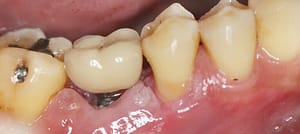

La perimplantite è una condizione infiammatoria che coinvolge i tessuti circostanti un impianto dentale. Si verifica quando c’è un’infiammazione del tessuto gengivale e osseo intorno all’impianto. Questa infiammazione può portare alla perdita di osso intorno all’impianto stesso e, se non trattata, può portare alla perdita dell’impianto dentale.

I sintomi della perimplantite possono includere gonfiore, arrossamento, sanguinamento gengivale, dolore e suppuratione intorno all’impianto. La perimplantite è spesso associata a una scarsa igiene orale, ma può anche essere influenzata da altri fattori come fumo, malattie sistemiche e problemi legati al posizionamento dell’impianto.

La perimplantite è un’infiammazione dei tessuti che circondano gli impianti dentali. In parole semplici, è una condizione che colpisce la salute degli impianti e può portare a problemi più gravi se non trattata correttamente.